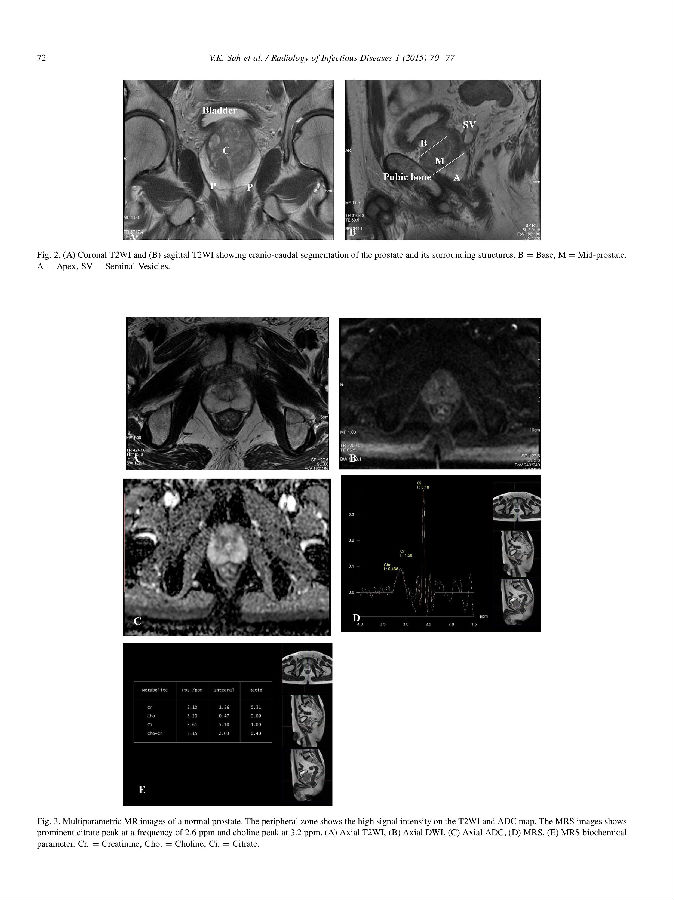

【学术推广】Multiparametric MR imaging in diagnosis of chronic prostatitis and its dif